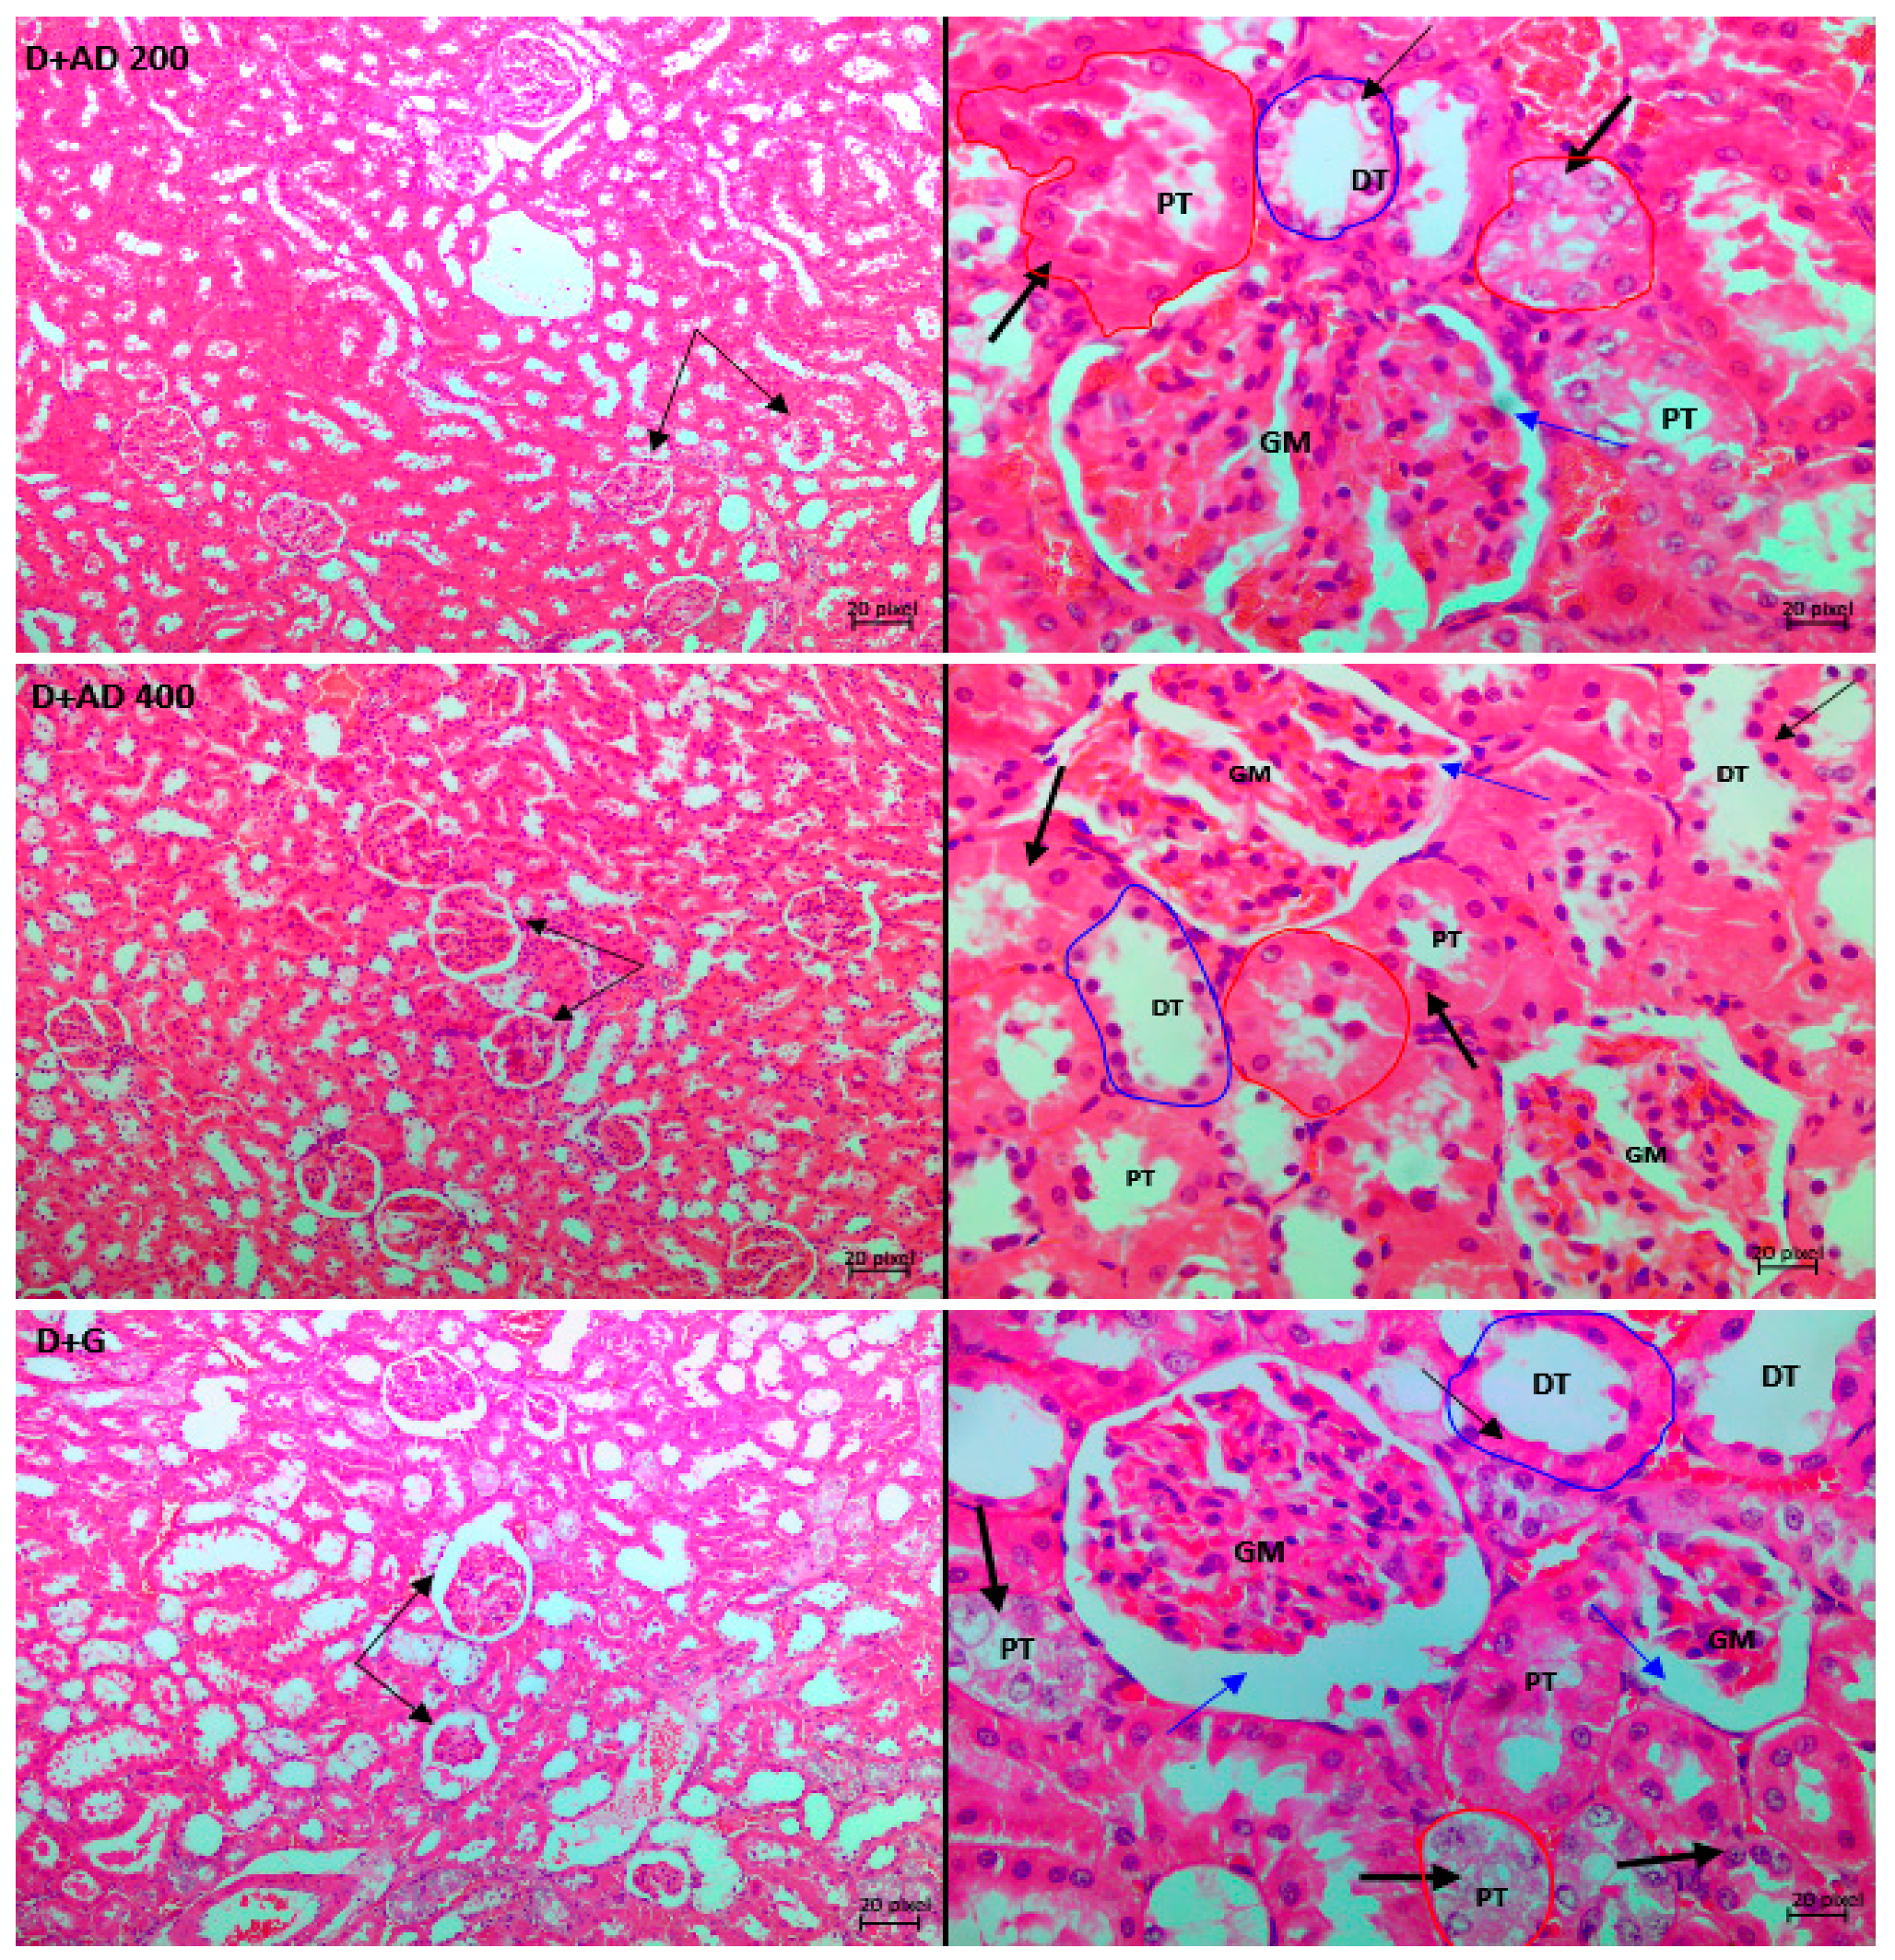

Figure 8 and Figure 9 are representative micrographs of the histological examination in the kidney and pancreas tissues of the normal, treated and untreated diabetic rats. Normal control and treated normal rats showed normal kidney architecture. Pathological conditions such as disappearing of the glomerular tuft comprising of the glomerular capillaries, podocytes and mesangial cells were observed in the kidney tissues of untreated diabetic rats. This led to widened Bowman’s space in the diabetic control rats when compared with the kidney of normal rats. Furthermore, endothelial cells were markedly detached from the basement membrane of the glomerulus in the untreated diabetic kidneys. Loss of tubular cells especially of the proximal tubules (PT) and increased blood flux were revealed in the kidney sections of untreated diabetic rats. Treatment with 200 mg/KgBW showed mild loss of tubular cells in the PT, while glomerular capillaries were clearly restored and less occurrence of glomerular shrinkage. Then, 400 mg/KgBW AD ameliorated glomerular and tubular damage in the kidney of treated diabetic rats. 400 mg/KgBW prevented loss of tubular cells of the proximal tubules and minimized loss of glomerular tuft in the treated diabetic rats as comparable to normal. The administration of glibenclamide showed widened Bowman’s space due to shrinkage of the glomerular tuft and moderate loss of tubular cells of the PT.

Figure 8.

Light photomicrographs of haematoxylin and eosin-stained kidney cortex of normal and diabetic rats. Double arrows are pointing to the bowman’s capsule and glomerulus (GM), while single thin arrows are showing the cells of the distal convoluted tubule (DT). The thick single arrows reveal the cells of the proximal convoluted tubule (PT). The blue arrows points at the bowman’s space. Magnification 10× (left) and 40× (right).

The major pathological alterations observed in the kidney tissues of untreated diabetic rats were disappearing glomerular tuft due to loss of podocytes, mesangial cells and glomerular capillaries. Also, loss of tubular cells especially the proximal tubules was observed in diabetic controls. This was ameliorated in the diabetic rats treated with AD. Apoptotic cell death plays a very crucial role in the loss of mesangial cells and podocytes [57,58]. Studies have reported the apoptotic death of renal tubular cells across various diabetic models such as mice, rats and humans [56]. One of the main causes of renal and glomerular apoptosis is increased inflammation. NF-ĸB, a pivotal inflammatory factor is activated in the podocytes, mesangial cells and tubular cells [10]. Increased expression and activation of NF-ĸB in these cells results in the production of pro-inflammatory factors and eventually apoptosis [47]. Decreased apoptosis was reported in NFκB tubular epithelial-specific knockout mice due to less activation of NFκB and reduced chemokine expression [48]. This supports the central role played by NF-ĸB in the apoptosis of the tubular and glomerular cells. A strong correlation has been established between NF-ĸB activation and the severity of renal disease [10]. In addition, the expression of Bcl2 is majorly detected in the proximal and distal tubules and in the capsular parietal cells in normal rats and humans [17]. In this study Bcl2 expression was significantly reduced in the kidney parenchyma of diabetic control rats, thereby aiding apoptosis. Figure 10 illustrates the suggested mechanisms and pathways that may be involved in the ameliorative effect of AD against kidney damage.